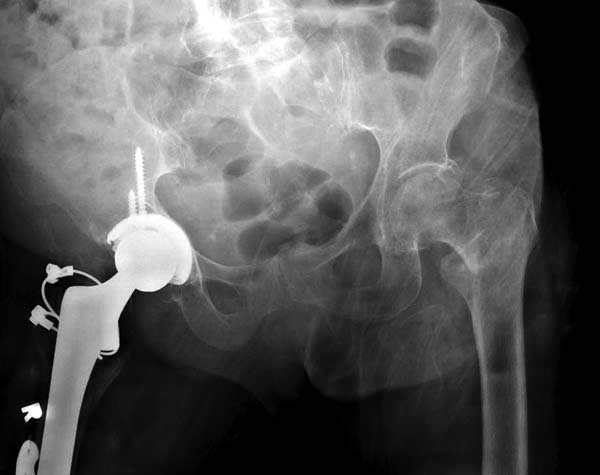

Третья операция-продолжения усилии "синьорами пэрами" по разрушению нормальной анатомии. Крест на головку! По видимому возраст позволяет биполярную конструкции, и при дефекте  calcar пошли на обычный цементный. Ягодичные мышцы потеряли связь с вертелом, т.е. отсутствует верхний удержатель, и результат “a Big Screw Up!” Снимки вызывают головокружение!

Такие “чужие осложнения” встречаются у всех и представляю банальный случай, который шаг за шагом показано как перерос в более сложный процесс... Больная 70 лет, множественные ко-морбидности, чрезвертельный перелом первоначально фиксирован Гамма 3. Осложнение в течение 6 недель, ревизия тотальной артропластикой и во время установки ножки обнаружена трещина диафиза (17), из малого доступа фиксация алло-графтом.